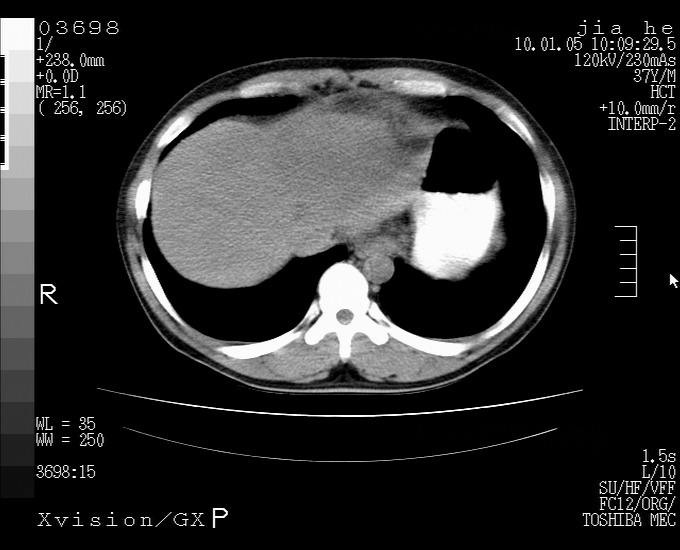

标题: CT23988:男,40岁,B超提示腹部肿物,请各位老师给看看。 [打印本页]

标题: CT23988:男,40岁,B超提示腹部肿物,请各位老师给看看。

左叶够大的,且与胰腺欠清晰,请增强扫描

考虑肝癌 请强化

肝左叶增大,建议增强扫描。

肝癌并腹膜后淋巴西结转移

2.脾大,肠系膜密度增高,有多发索条影,胰腺边缘毛糙,腹膜增厚,推测有肝硬化,门脉高压,腹膜炎和/或胰腺炎

3.肝左叶巨大站位,并腹腔淋巴结肿大,肝癌或肝间叶来源恶性肿瘤,也不排除大网膜间质瘤侵及肝左叶

建议:增强或磁共振

肝硬化、脾大;胃底静脉曲张;是否门脉高压所致,建议进一步检查。

还有个异位胆囊。临床资料太少,肿瘤、左叶发育异常、肝硬化。不过看密度是个低密度为主的,新生物倾向于第一位。强化吧!

考虑肝左叶外侧段癌并腹膜后淋巴结转移.建议增强进一步检查.